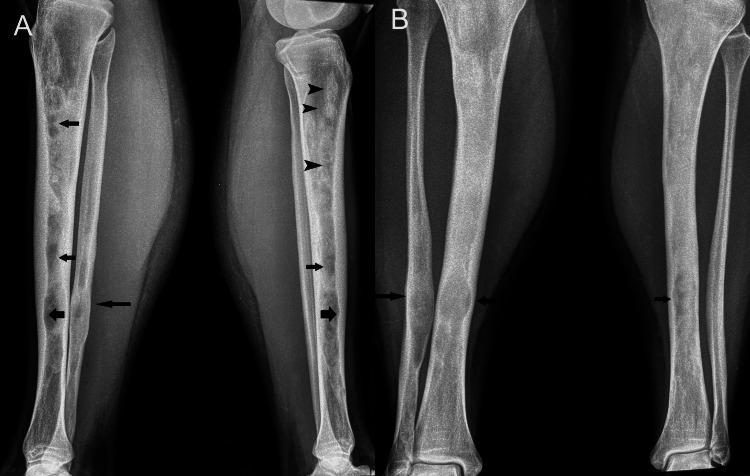

Mazabraud syndrome is a rare condition characterized by the coexistence of fibrous dysplasia (FD) and intramuscular myxomas. A 46-year-old woman, initially diagnosed with polyostotic FD at the age of 23, developed a palpable mass on her left arm 15 years later, which proved to be an intramuscular myxoma. A diagnosis of Mazabraud syndrome was made. Over the following two decades, she developed additional intramuscular myxomas. The patient denied surgical excision of the soft tissue lesions and was managed conservatively for symptomatic FD. Radiologic imaging, including MRI and ultrasound, played a crucial role in the diagnosis and the assessment of disease progression. Although both FD and myxomas are benign musculoskeletal abnormalities, close follow-up of the patients is essential to monitor changes in the number, distribution, and extent of lesions that may occasionally undergo malignant transformation. This case underscores the importance of early detection and long-term follow-up of patients with FD who may present with, or eventually develop, intramuscular myxomas, comprising Mazabraud syndrome.

马扎布劳德综合征是一种罕见疾病,其特征为骨纤维发育不良(FD)和肌内黏液瘤并存。一名46岁女性,23岁时最初被诊断为多骨型FD,15年后左手臂出现一个可触及的肿块,经证实为肌内黏液瘤。遂作出马扎布劳德综合征的诊断。在接下来的二十年里,她又出现了其他肌内黏液瘤。该患者拒绝手术切除软组织病变,对有症状的FD采取保守治疗。包括MRI和超声在内的放射学成像在疾病诊断和病情进展评估中发挥了关键作用。尽管FD和黏液瘤均为良性肌肉骨骼异常,但对患者进行密切随访对于监测可能偶尔发生恶变的病变的数量、分布和范围变化至关重要。该病例强调了对可能出现或最终发展为肌内黏液瘤(构成马扎布劳德综合征)的FD患者进行早期检测和长期随访的重要性。